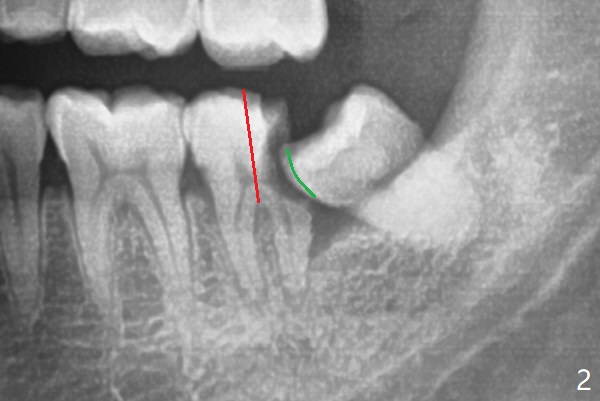

To extract #18, the tooth has to be sectioned (Fig.2 red).  The mesial portion is removed easy, while the distal one requires trimming the mesial surface of #17 (Fig.2 green).